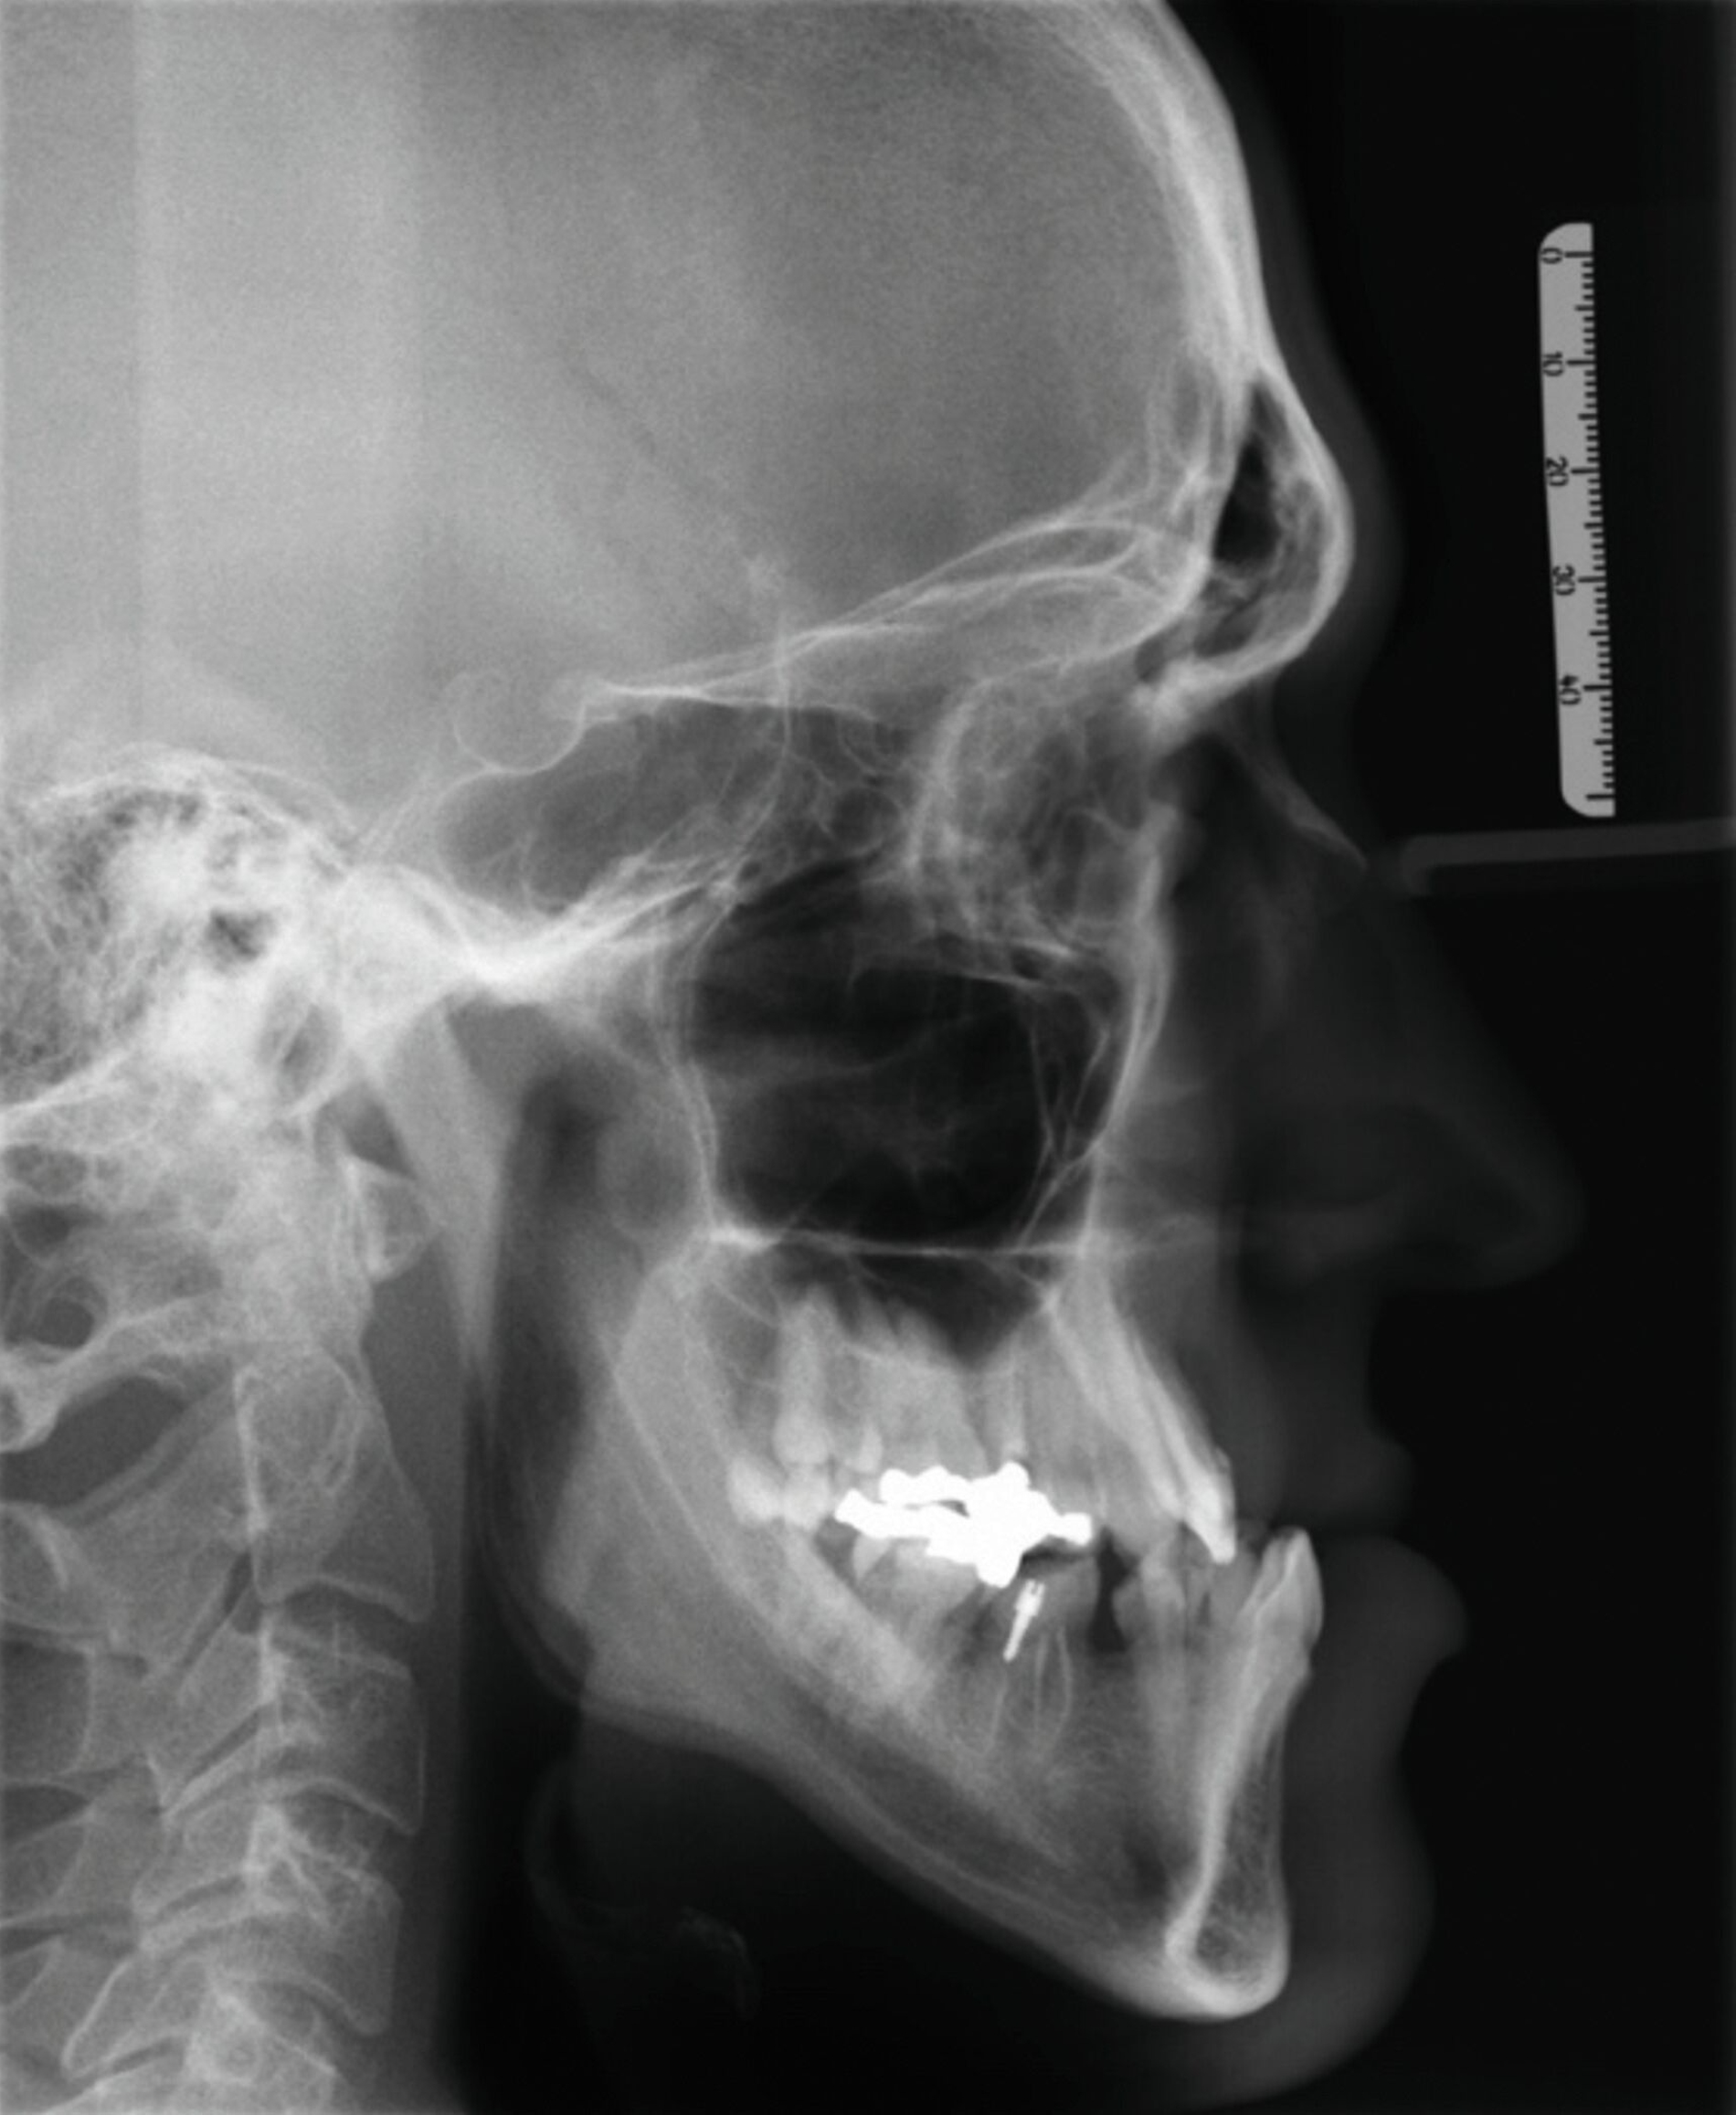

Die Auswertung der Fernröntgenseitenaufnahme ergab eine orthognathe Maxilla (SNA: 80,7°) und eine prognathe Mandibula (SNB: 90°) bei Vorliegen eines dolichofazialen Wachstumsmusters (Abbildung 4). Zudem deuteten die Ergebnisse auf eine mesiale basale Diskrepanz hin (ANB: -9,2° und WITS: -8,2 mm). Die Oberkieferfrontzähne zeigten eine orthoaxiale Stellung, während die Unterkieferfrontzähne einen ausgeprägten lingualen Kippstand aufwiesen. Die kephalometrischen und die klinischen Befunde deuteten somit auf ein Long-Face-Syndrom hin.